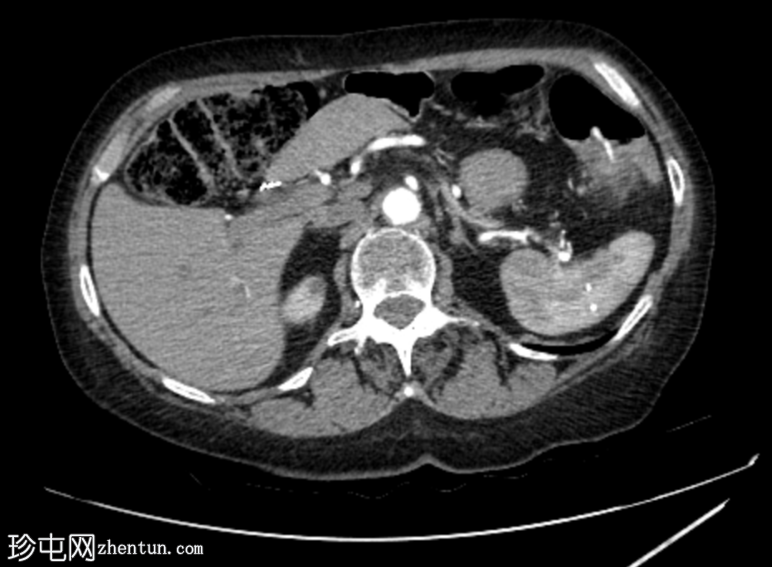

2.png

轴位增强扫描

动脉期

动脉早期可见造影剂外渗,冠状位和矢状位最大强度投影(MIP)图像也可见,位于憩室炎同一部位,符合活动性出血表现。

随后的门静脉期和延迟期图像显示造影剂在结肠腔内积聚。

本病例还展示了使用消化道出血CT扫描方案的重要性,该方案包括非增强期和不使用口服造影剂,以便在早期动脉期清晰识别活动性造影剂外渗(活动性出血)的部位,正如本病例所示。

肠腔内造影剂外渗是活动性出血的标志,通常表现为增强血管的衰减,并且其表现会随时间变化,正如本病例所示,通常从动脉期到门静脉期,出血量增加并向远端延伸。